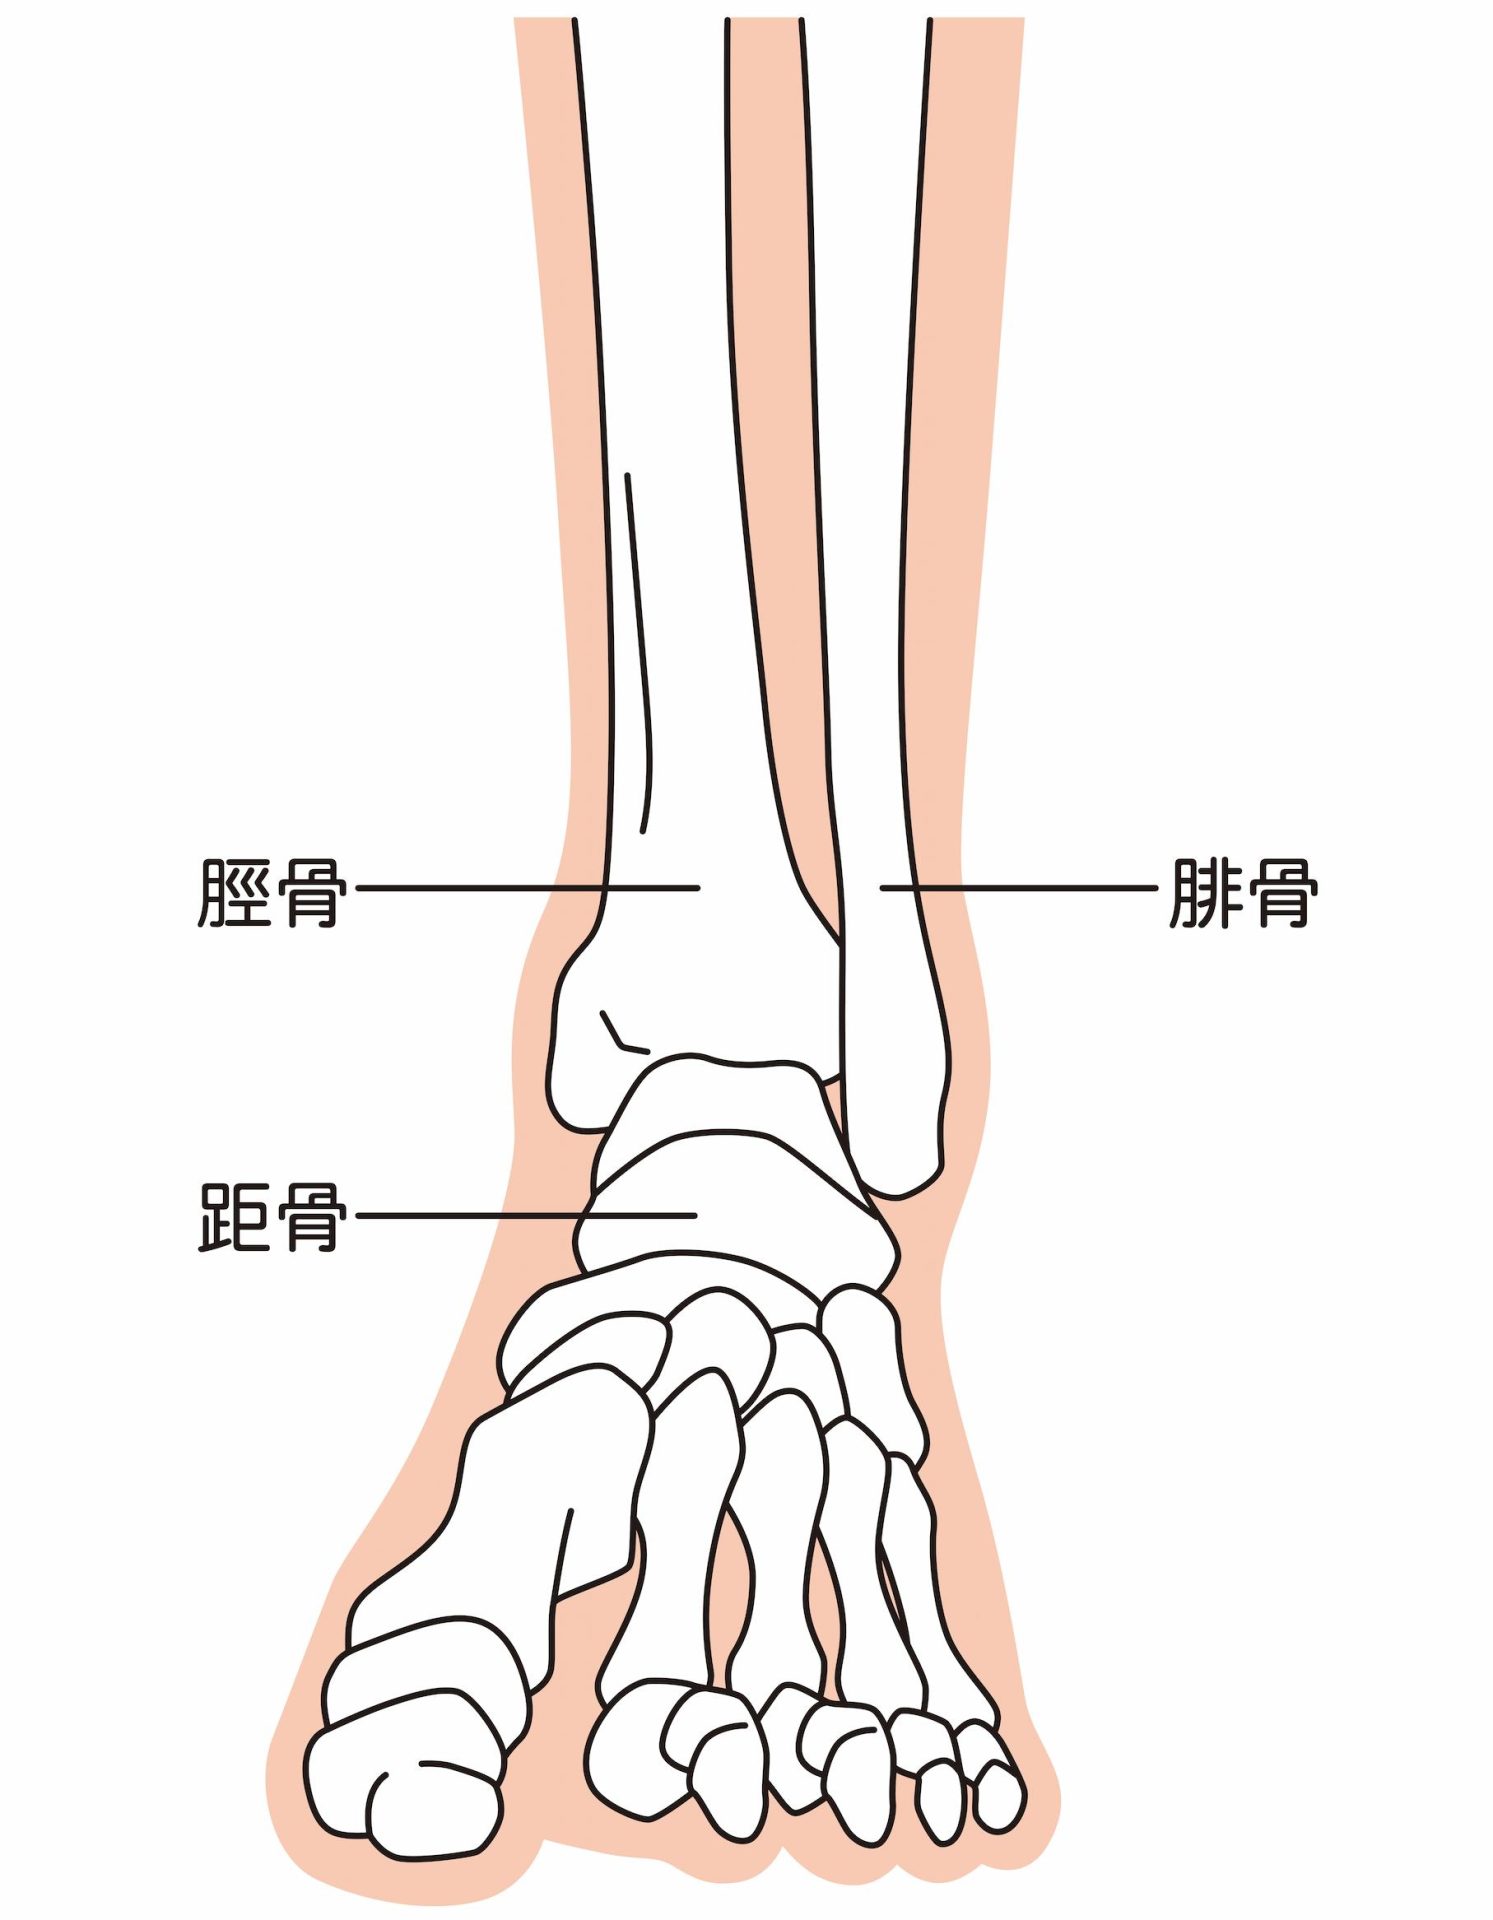

足関節とは、一般的に足首と呼ばれている箇所のことです。かかとの上にある距骨(きょこつ)、すねの骨である脛骨(けいこつ)、その外側を平行する腓骨(ひこつ)の3つの骨から構成されています。周囲は軟骨(なんこつ)や靭帯(じんたい)に覆われており、つま先を上下に動かしたり、足と体をつなぐ役割を果たしています。足関節のつくりについて、それぞれの役割をみていきましょう。

距骨(きょこつ)、脛骨(けいこつ)、腓骨(ひこつ)の3つが面している関節を距腿(きょたい)関節といいます。距腿(きょたい)関節とは、脛骨(けいこつ)と腓骨(ひこつ)の凹面に、距骨(きょこつ)の凸面がはまって形成されている関節のことです。ドアの蝶番(ちょうつがい)のように動くため、蝶番(ちょうつがい)関節とも言われています。足首を上下に動かすときに使われる関節です。